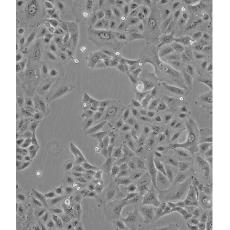

產(chǎn)品名稱 A549/DDP

中文名稱 人肺腺癌耐順鉑株

細胞種屬 Homo sapiens, human

生長特性 adherent

培養(yǎng)基 RPMI-1640+10% FBS+1-2μg/ml DDP+1% P/S

形態(tài)特征 epithelial

傳代方法 1:2-1:3